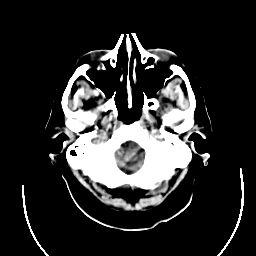

CT Study #3 -- Slice #3